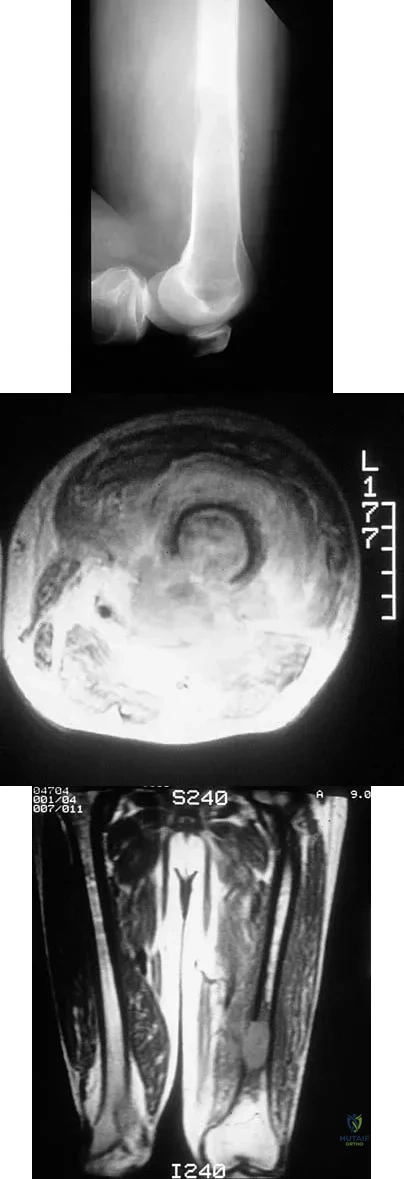

Figures 48a through 48c show the lateral radiograph and MRI scans of a 60-year-old man who has had pain in his thigh for 1 month. The next most appropriate step in management should consist of